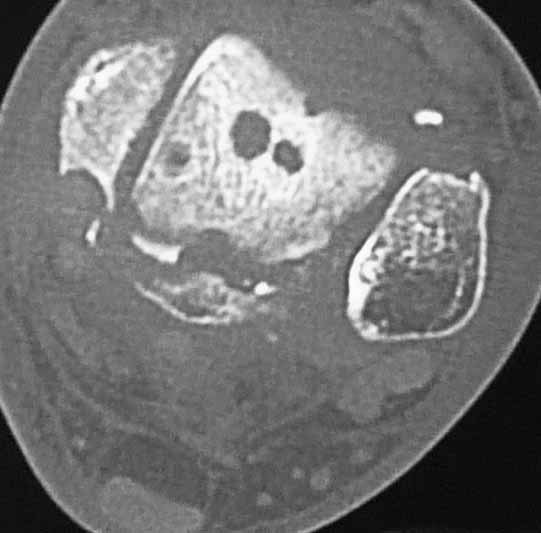

Уважаемые коллеги. Не так давно на форуме коротко обсуждались возможные последствия трансартикулярной фиксации голеностопного сустава при переломовывихах лодыжек.

На днях довелось увидеть КТ после удаления спиц. Картинки наглядные и, практически, не нуждаются в комментариях. Одна из спиц, кстати, проходила через фрагмент заднего края.

Картинки наглядные и, практически, не нуждаются в комментариях. Одна из спиц, кстати, проходила через фрагмент заднего края

Снимки являются доказательством важности защиты суставного хряща от грубой интервенции, и особенно от тех неудачных многочисленных попыток фиксации спицами, когда спицы оставляют на поверхности сустава непоправимые следы. Понятно, что повреждение целости хряща приводит к развитию хондролизиса, артрозу и т.д....

Понятно, огромные “дырки” в суставе не от хорошей жизни, хотя на самом деле “увеличенная картина” на КТ срезах может оказаться банальным проколом от 1,2 или 2 мм спиц. Большие неприятности, когда спицы находятся долго, и когда лизис вокруг спицы принимает большие размеры. А так - не стал бы драматизировать единичные спицы, установленные на короткое время, потому что такие “интервенции” сустава у большинства больных проходят без клинических проявлений.

А вот без надобности проведенные (через фрагменты заднего края) спицы - больше, чем технический брак, и часто такие ошибки, как назло, приводят к инфицированию всего сустава.